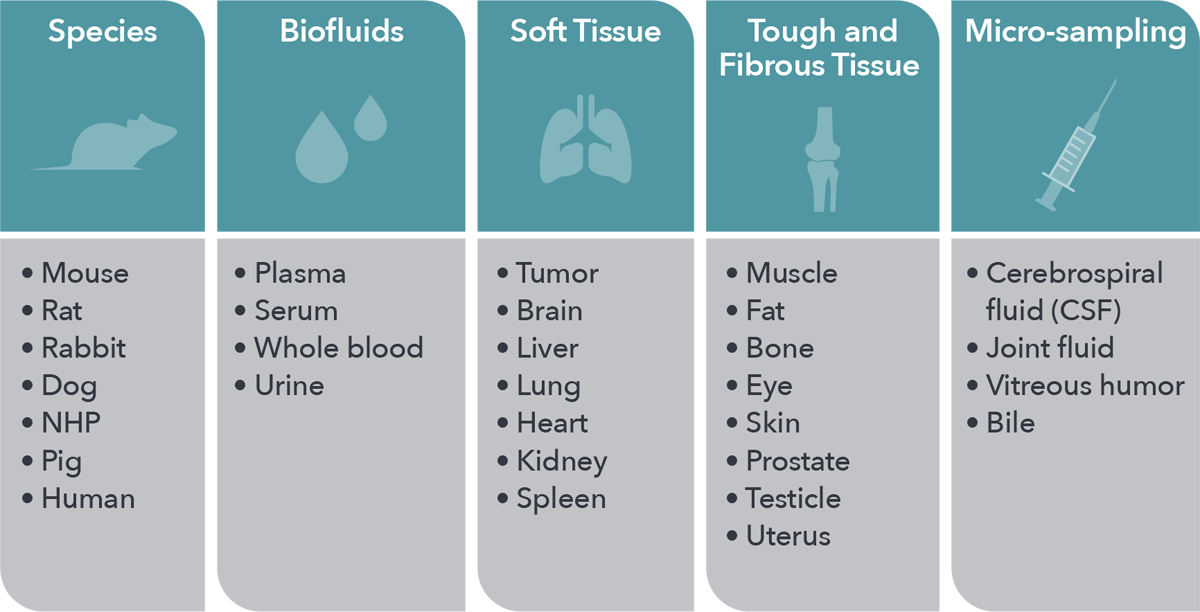

Inform your drug development by leveraging our unparalleled in vivo expertise and models, with a range of animal species and tissue types amenable to all in vivo PK needs. High quality data is assured for every study through extensive quality assurance systems.